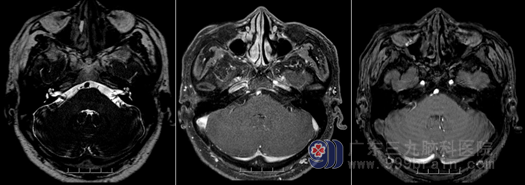

后来实在是眼皮跳得烦,为了进一步的检查与治疗,吴先生来到了广东三九脑科医院,被诊断为“左侧面肌痉挛”,收治到神经外十科。吴先生的磁共振结果显示:两侧面神经以及左侧三叉神经颅内段均存在关系密切的小血管影。

外十科主任欧阳辉教授向吴先生解释,肿瘤压迫、血管压迫面神经等因素可引起面肌痉挛,吴先生头颅检查未发现颅内占位性病变,从吴先生的磁共振结果来看,考虑是血管的对面神经的压迫导致面肌痉挛的诊断,“眼皮跳”是面肌痉挛的症状,无所谓凶吉,而应该手术治疗。对于吴先生的情况,欧阳辉主任提出了面神经微血管减压术的手术方案,即通过开颅找到肇事(责任)血管,并且对血管与面神经进行钝性分离,并在两者之间是垫入特制的棉片(Teflon棉丝)将神经和血管进行隔开,解除血管对面神经的压迫,从而根治面肌痉挛。